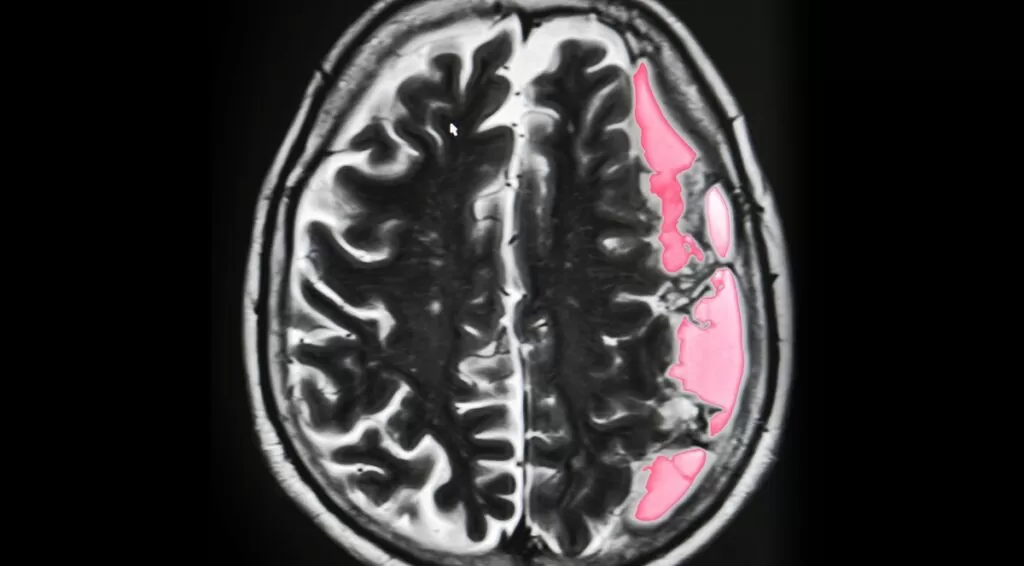

التشخيص

يتم التشخيص المبدئي على الفحص البدني للمريض، بالإضافة إلى بعض الاختبارات التشخيصية للتأكد تماماً من التشخيص، وتشمل:

- التصوير بالرنين المغناطيسي.

- التصوير المقطعي المحوسب.

- تصوير الأوعية الدموية بالدماغ بالرنين المغناطيسي.